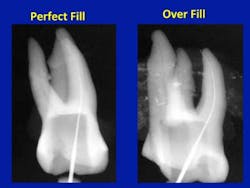

We had clues to the answer to the problem in the literature for many years, but no one connected the dots. The literature stated that the radiographic apex and the anatomic apex did not coincide in more than 50% of the canals. Recently, El Ayouti et al. showed that the anatomic apex was short of the radiographic apex in 88% of the canals,and in 5% of the canals the anatomic foramen was more than 2 mm short of the radiographic apex. (1) In this article, they stated that root fillings extending to the radiographic apex are actually over fillings in most of the canals. Here is the answer to that perplexing clinical problem. The x-ray looks perfect and the gutta-percha is right at the radiographic apex, so why does the tooth hurt? The answer is that in the clinical reality (figure 1), the anatomic apex does not coincide with the radiographic apex and, consequently, the instrumentation is long and the filling material (gutta-percha and sealer) are both past the anatomic apex.

In figure 1, we see that the file has been pushed through the anatomic apex to reach the radiographic apex. It goes through the periodontal ligament and bone to get there. The dentist now instruments to this incorrect measurement. The result is a lot of postoperative pain once the anesthesia wears off. Then, to make matters worse, the gutta-percha is now pushed through the anatomic apex and sealed into the ligament and bone. No wonder it sometimes does not heal and often causes the patient discomfort.